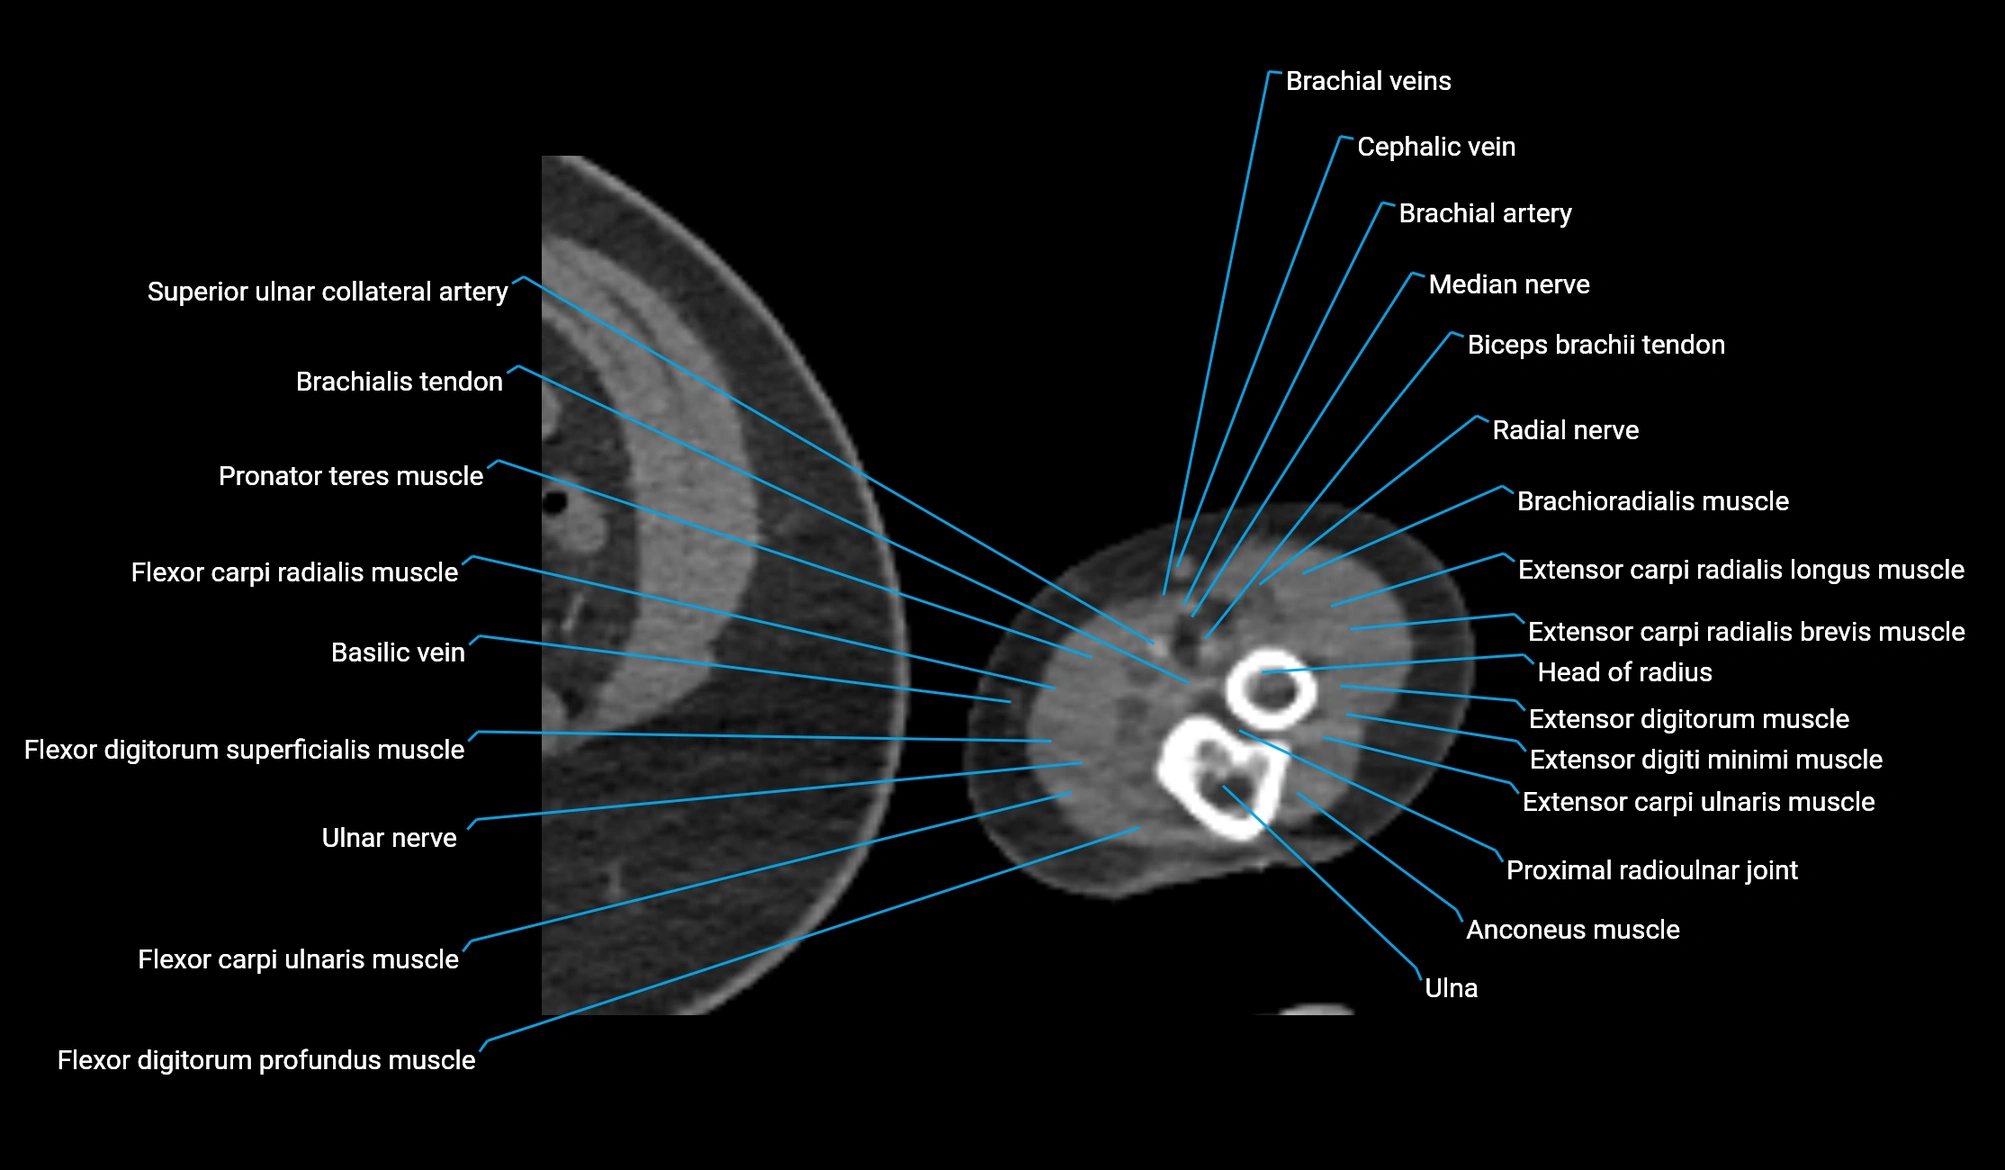

CT image